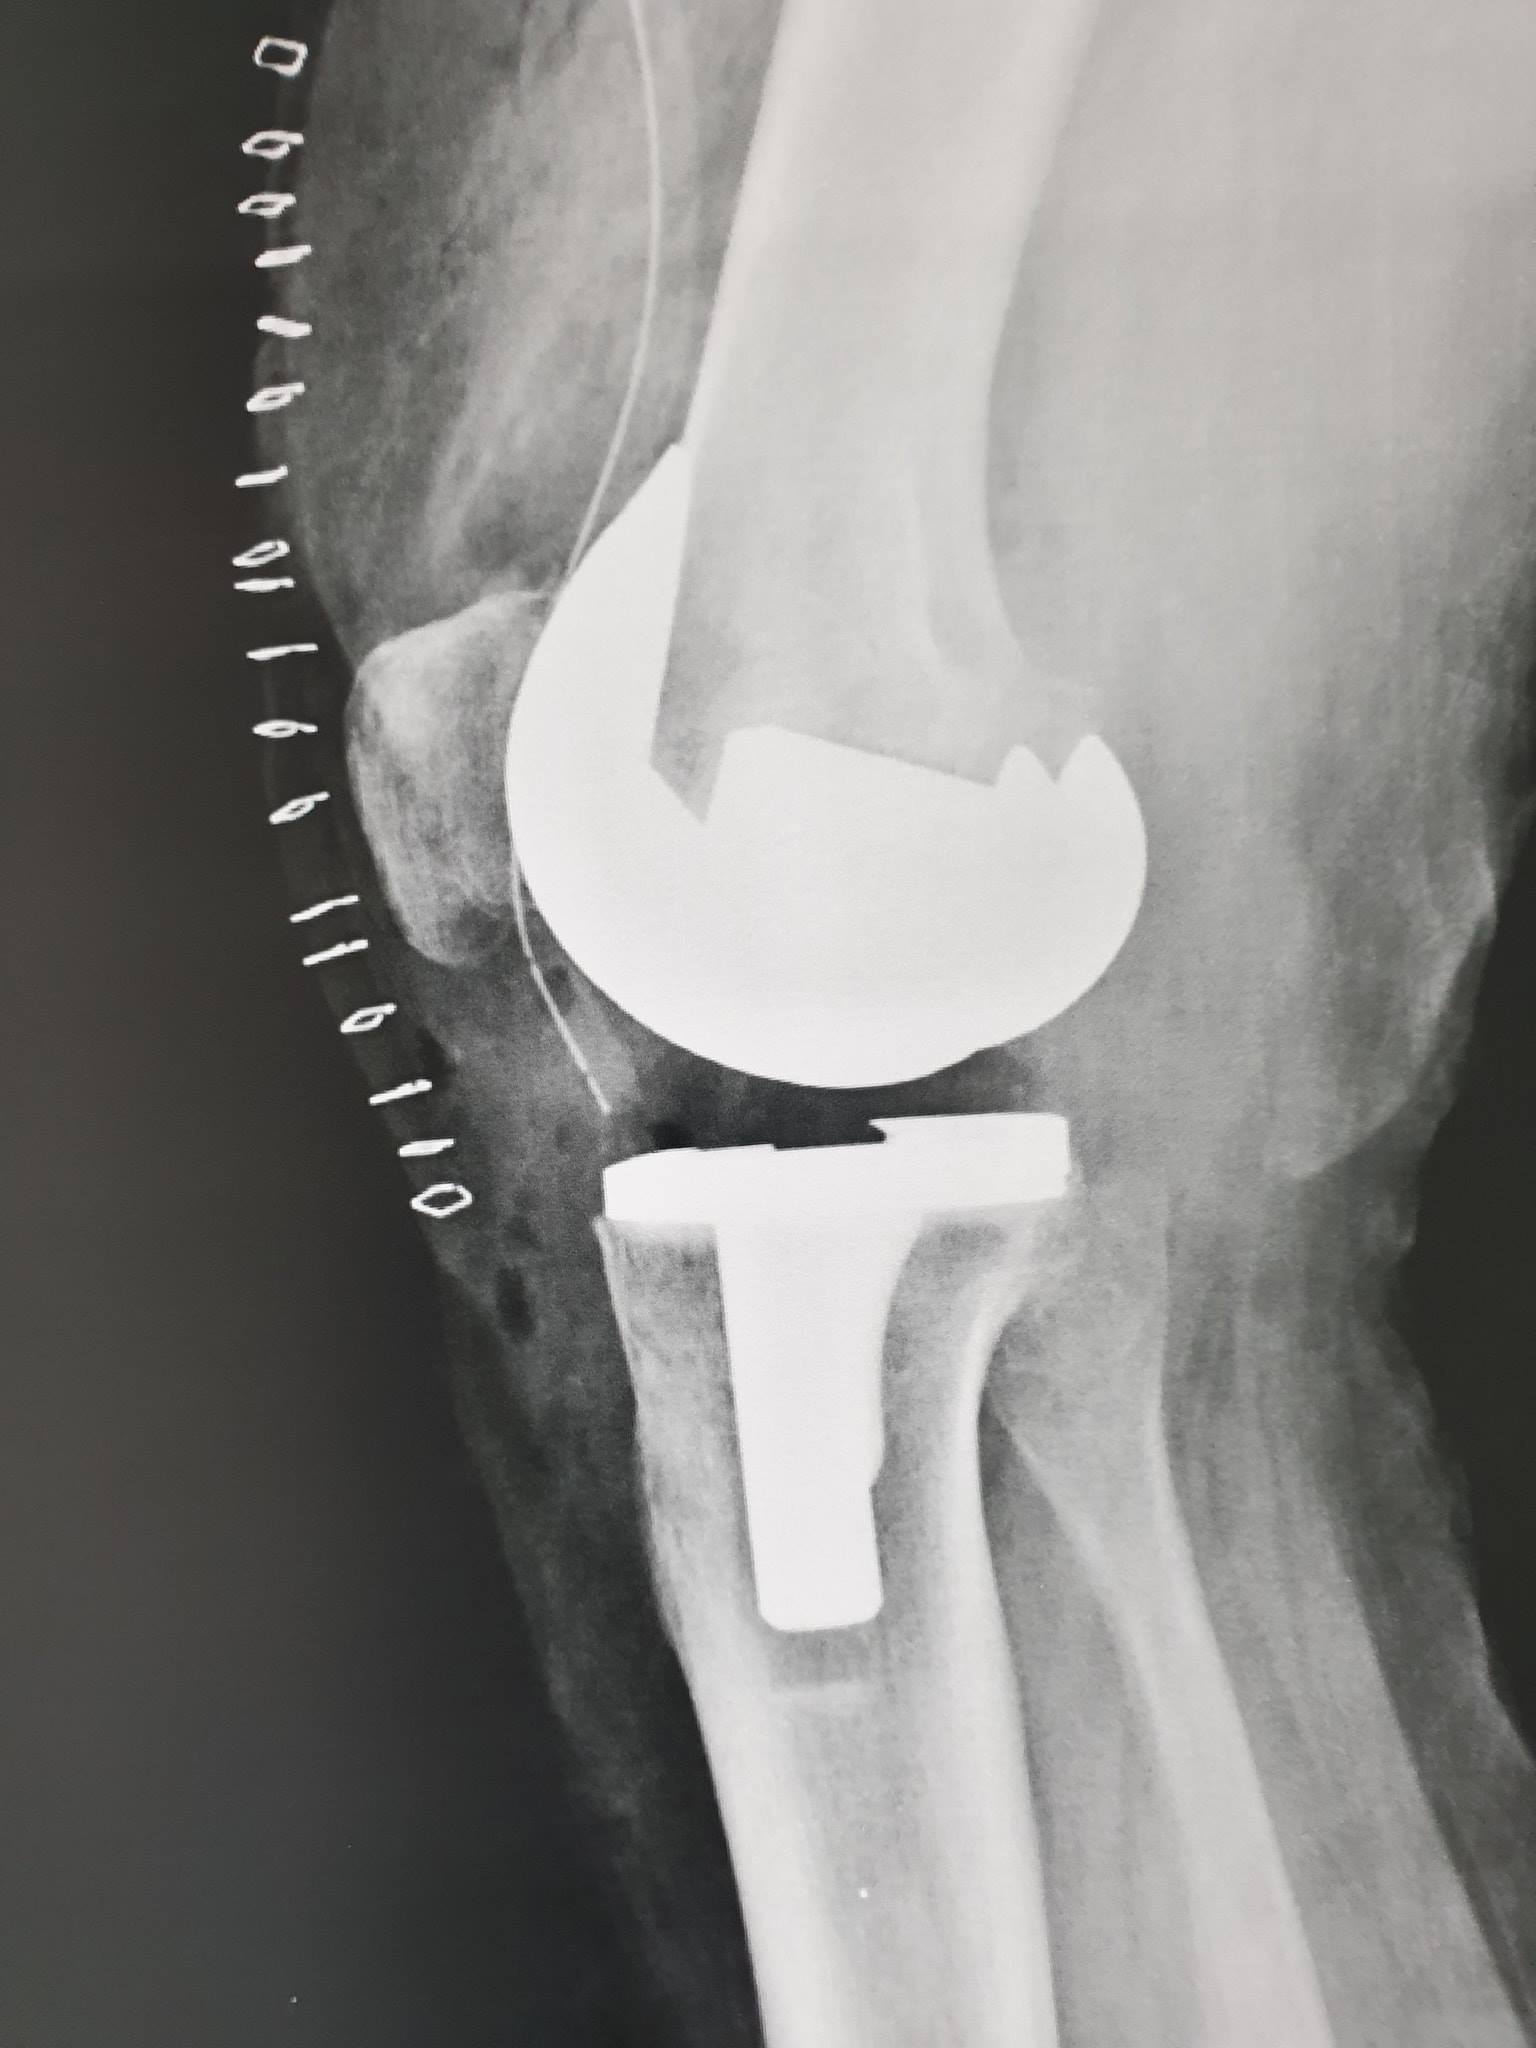

زراعة المفاصل الصناعية ورك و